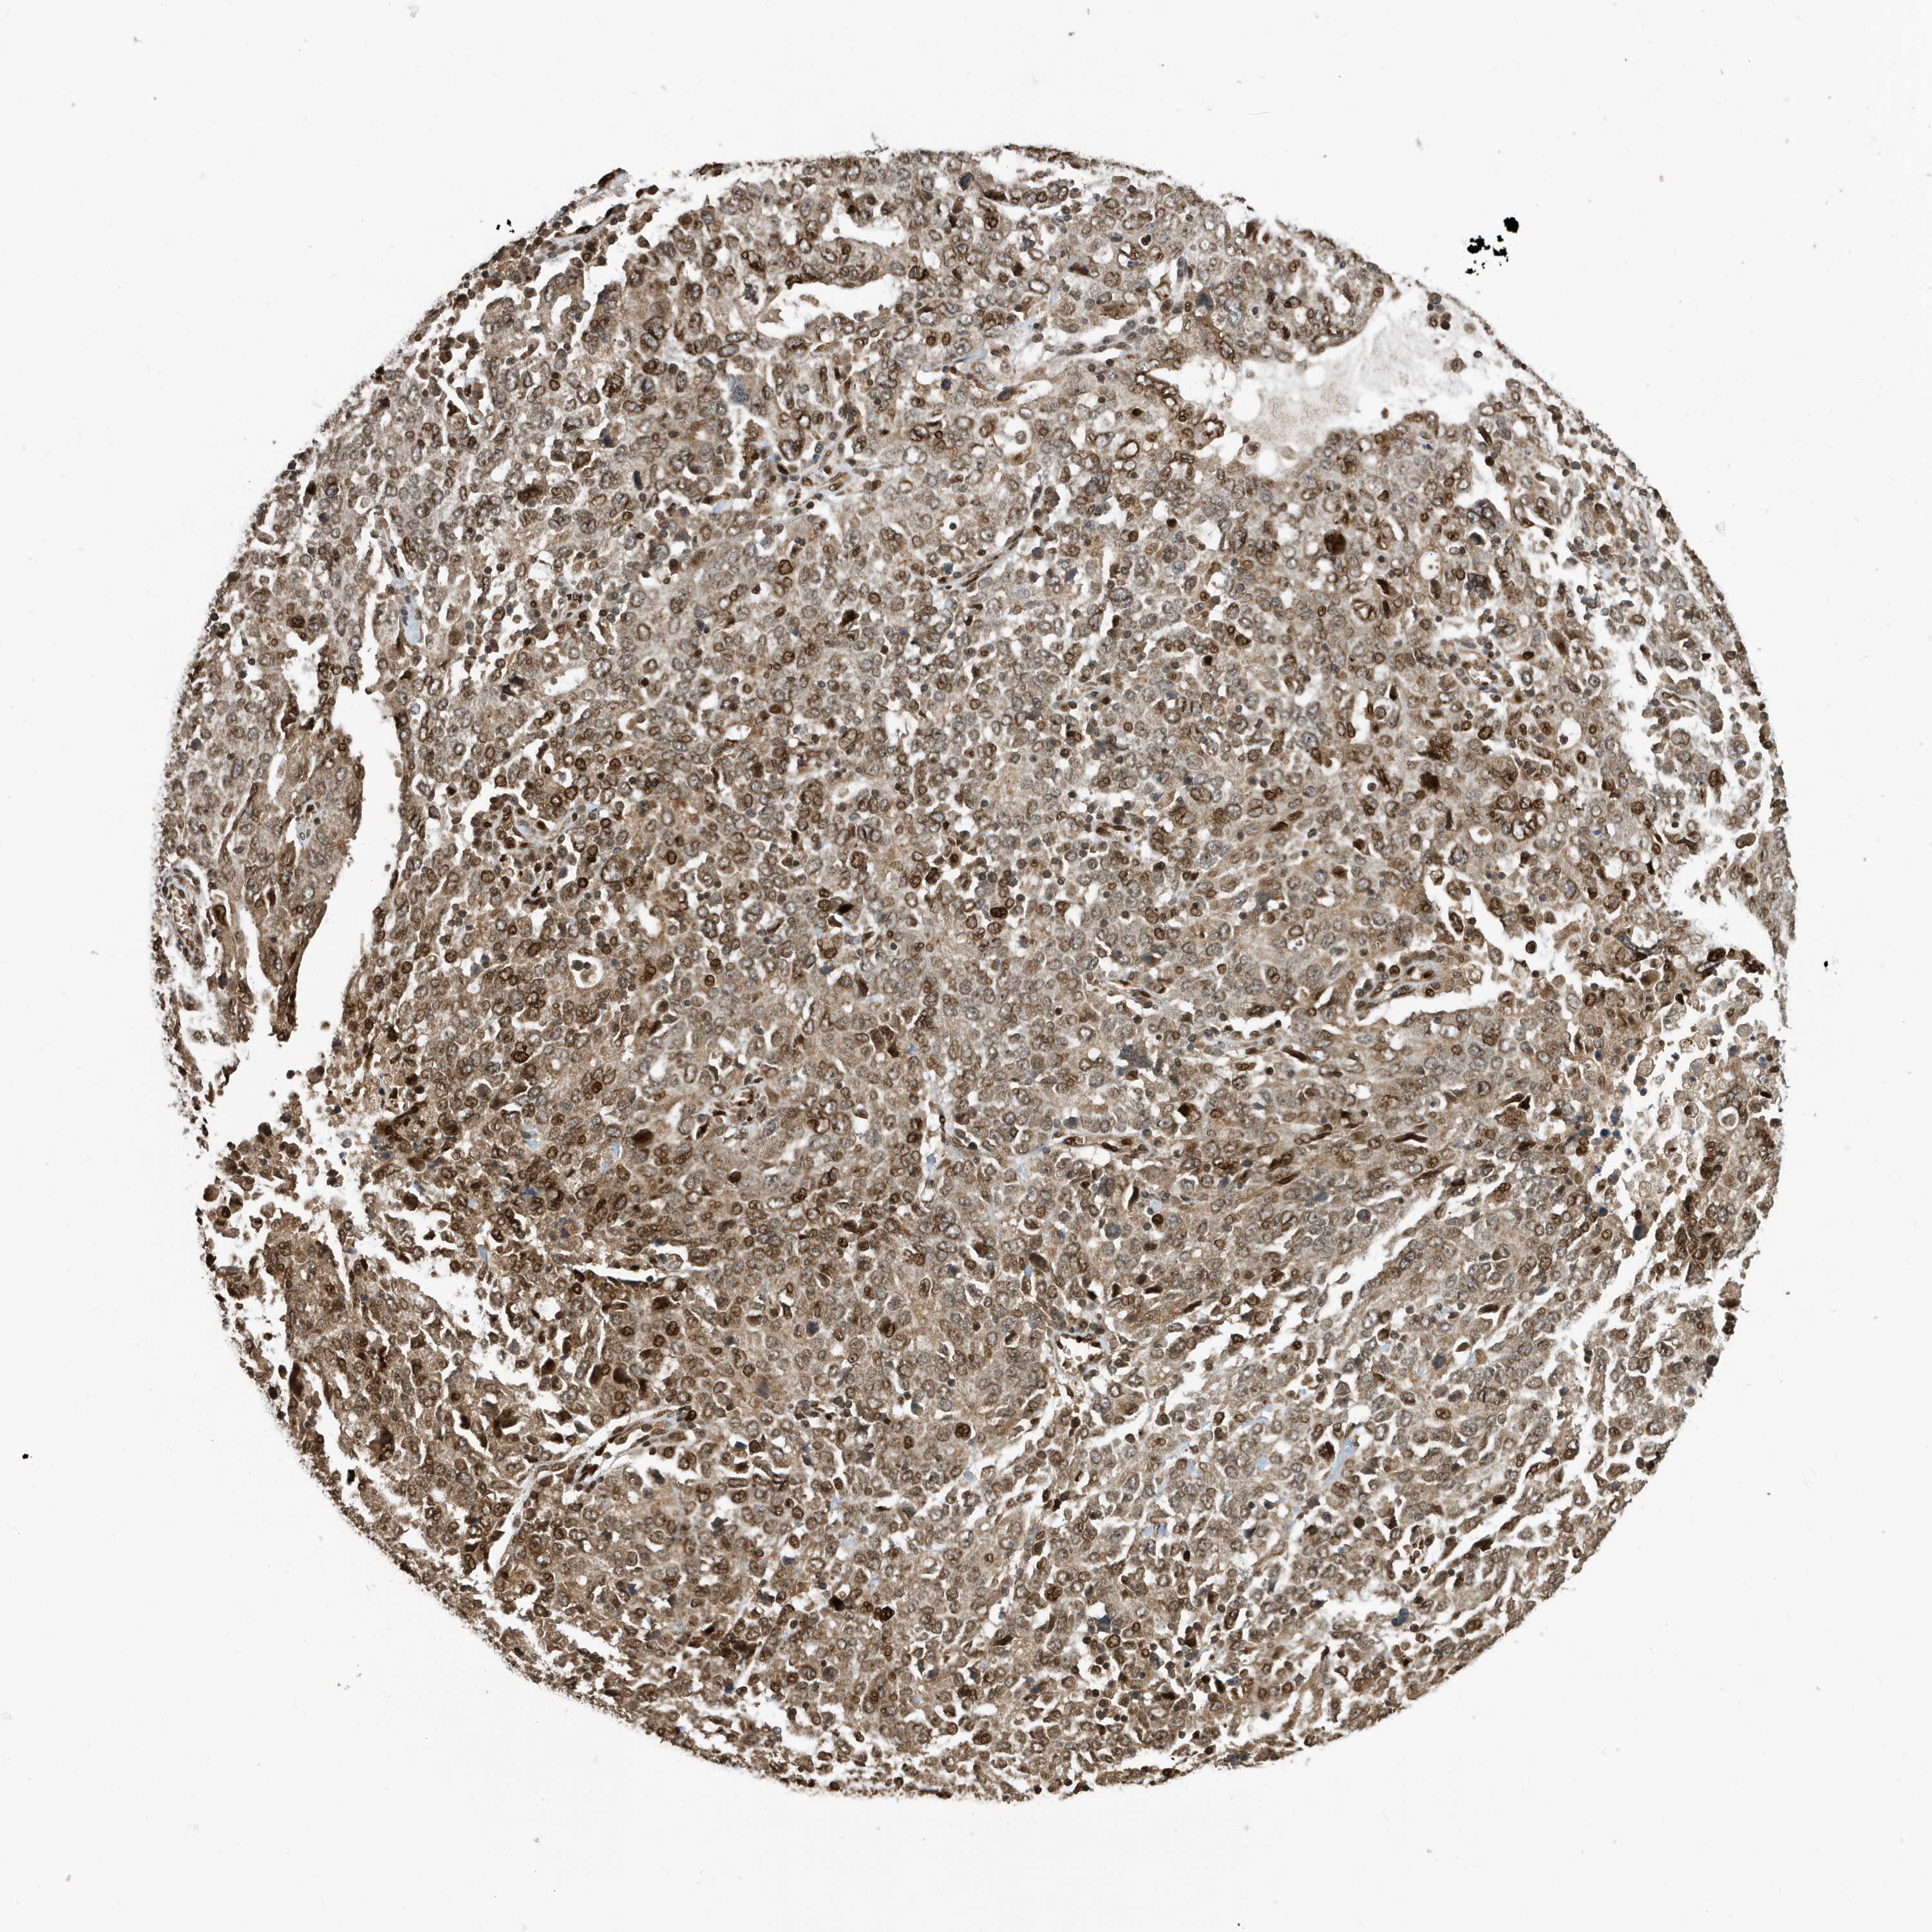

OVARIAN CANCER - Protein expressioni

A mouse-over function shows sample information and annotation data. Click on an image to view it in a full screen mode. Samples can be filtered based on level of antibody staining by selecting one or several of the following categories: high, medium, low and not detected. The assay and annotation is described here.

Note that samples used for immunohistochemistry by the Human Protein Atlas do not correspond to samples in the TCGA dataset.

Antibody stainingi

Antibody staining in the annotated cell types in the current human tissue is reported as not detected, low, medium, or high, based on conventional immunohistochemistry profiling in selected tissues. This score is based on the combination of the staining intensity and fraction of stained cells.

Each image is clickable and will lead to virtual microscopy that enables deeper exploration of all samples and also displays staining intensity scores, fraction scores and subcellular localization as well as patient and tissue information for each sample.

Antibody CAB034070

Staining

High

Medium

Low

Not detected

Intensity

Strong

Moderate

Weak

Negative

Quantity

>75%

75%-25%

<25%

None

Location

Nuclear

Cytoplasmic/membranous

Cytoplasmic/membranous,nuclear

Cystadenocarcinoma, serous, NOS

Carcinoma, endometroid

Cystadenocarcinoma, mucinous, NOS

Carcinoma, NOS